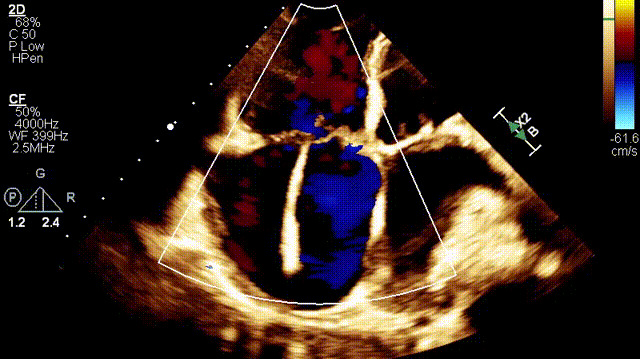

植入前超聲

手術在全麻狀態(tài)下開展,此次手術采用經右側頸靜脈入路的方式將輸送器送入患者心臟內,在TEE及DSA引導下調整輸送器頭端角度,使得輸送器與三尖瓣瓣環(huán)平面垂直。在輸送器進入右心室后釋放室間隔錨定裝置,而后釋放瓣葉夾持件(2個耳片結構)成垂直狀態(tài)。在TEE及DSA確定夾持件固定至三尖瓣葉根部且位于右室側后釋放人工瓣心房側盤片。隨后調整瓣膜同軸性以及室間隔錨定件位置(貼合室間隔),前推藏針管并固定,進而釋放室間隔錨定裝置,并再次確認瓣膜位置、穩(wěn)定性及同軸性,合攏輸送鞘后撤出輸送器,完成LuX-Valve Plus人工三尖瓣瓣膜的植入。